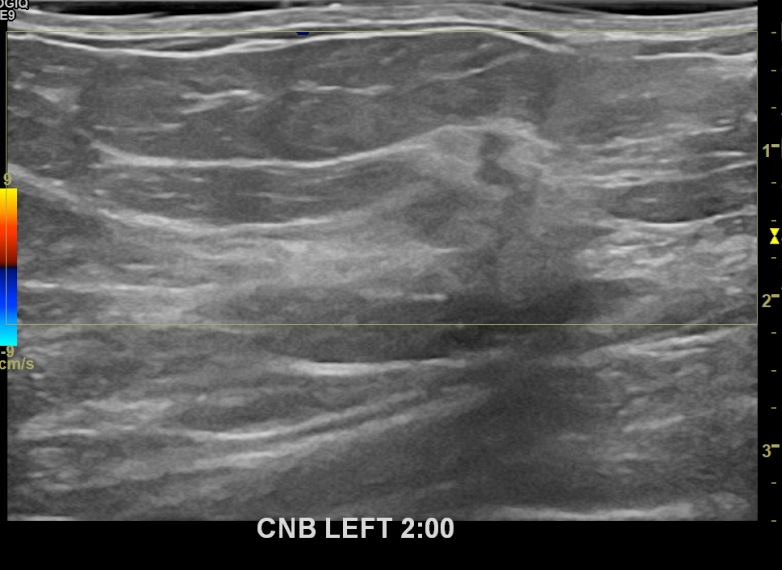

아산유외과개원후 673번째 유방암진단

상기환자 외부검사상 이상소견으로 내원하신 40대여성으로 좌측에 의심스러운혹 조직검사시행해 유방암 진단되었습니다.